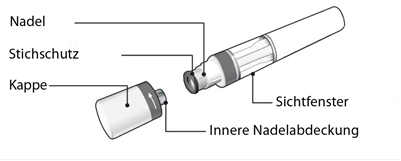

Abbildung A: Teile des Hyrimoz SensoReady Fertigpens

In Abbildung A ist der Fertigpen mit abgezogener Kappe dargestellt. Entfernen Sie die Kappe erst unmittelbar vor der Injektion.